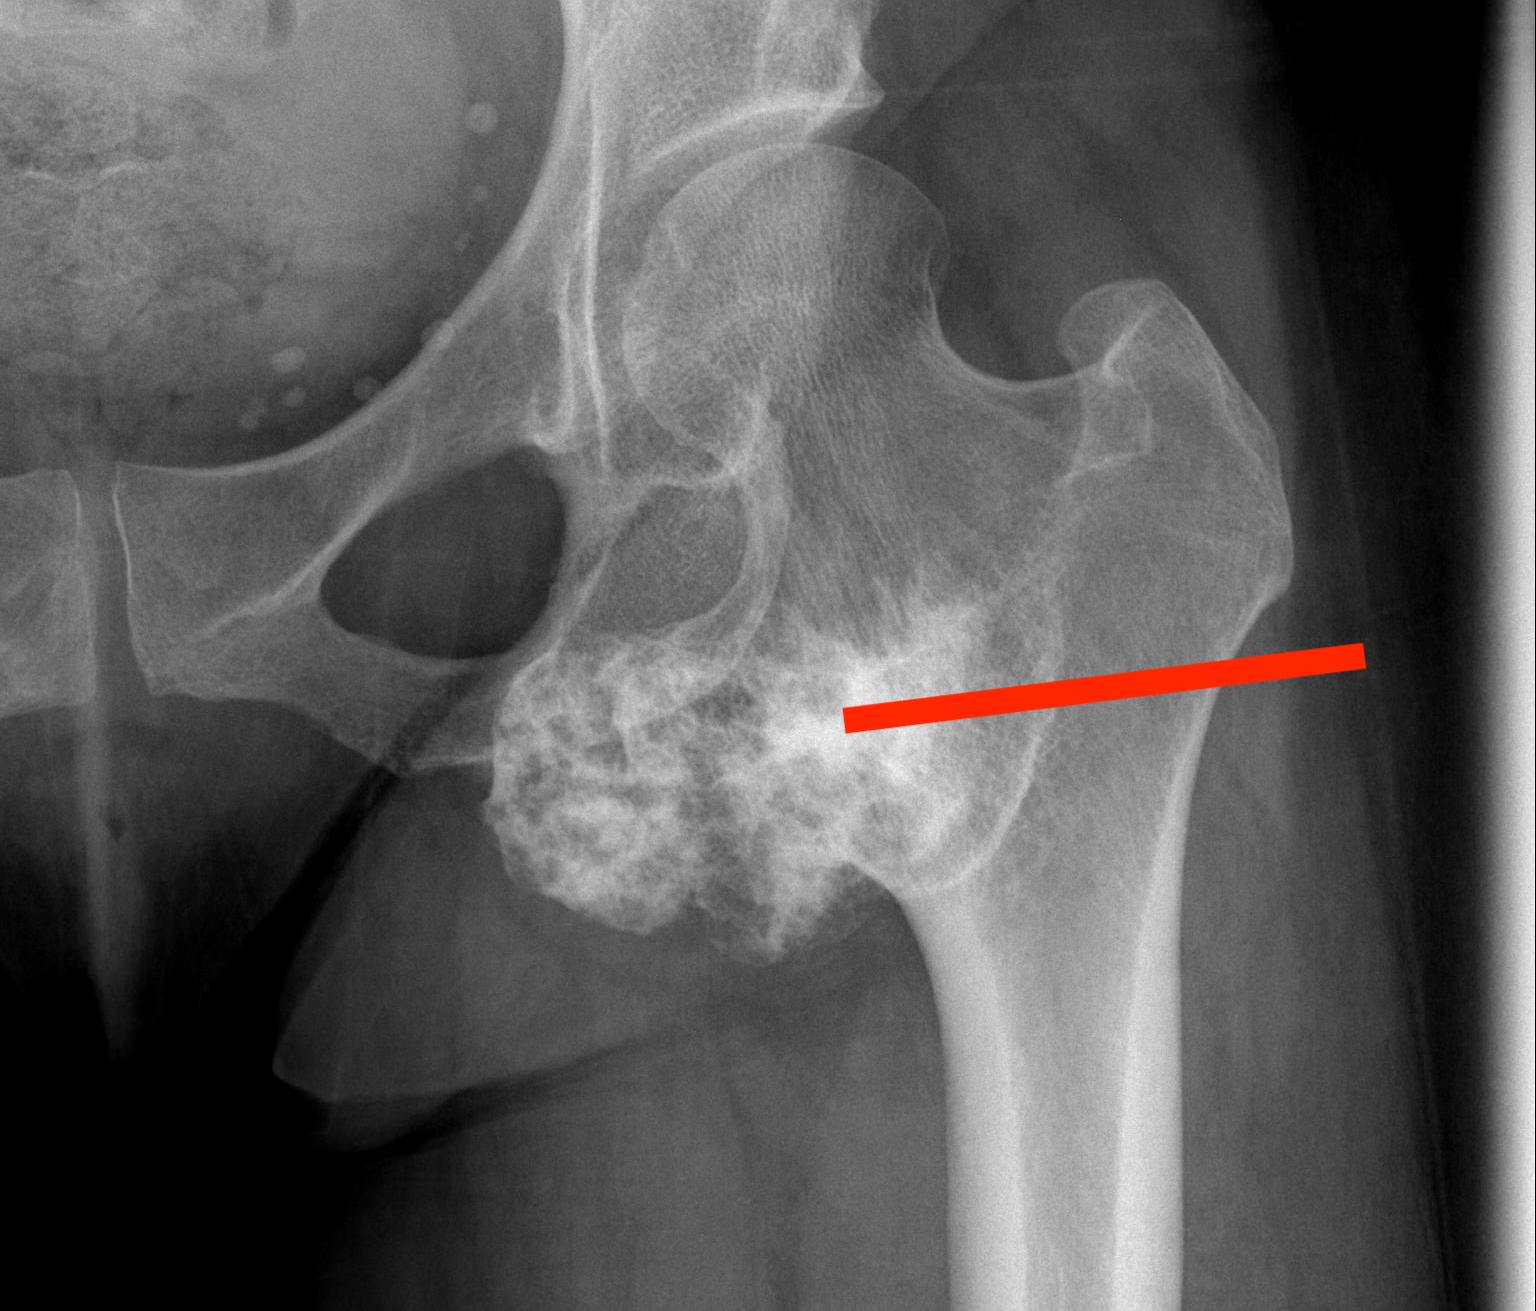

2.  Subtrochanteric / femoral shaft

- lateral approach

- aim anterior or posterior to lateral intermuscular septum depending on compartment

- avoid rectus femoris / vastus intermedius

- ok to resect part of vastus lateralis or biceps femoris

Tumour Subtrochanteric FemurFemoral Shaft Bony LesionFemoral shaft biopsy